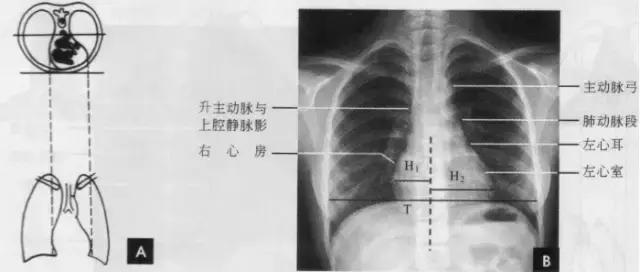

七、心脏大血管

心脏和大血管在平片上的投影彼此重叠,仅能显示各房室和大血管的轮廓,不能见到其内部结构和分界。因此,必须用不同的位置投照,才能使各个房室和大血管的边缘显示出来。常用后前位、右前斜位、左前斜位和左侧位的摄影,分述如下:

(一)后前位

正常心影2/3位于中线左侧,1/3位于右侧,心尖指向左下,心底部朝向右后上方,形成斜的纵轴。后前位心脏大血管有左右两缘:心右缘分为两段,上段为升主动脉与上腔静脉的总合影,在幼年和青年人边缘主要为上腔静脉影向上延伸,在老年人常见纡曲延长的升主动脉影突出于上腔静脉边缘之外;心右缘下段为右心房所构成,有时在心瞩角内可见一向外下方倾斜的三角形影,为下腔静脉攻肝静脉影,深吸气时明显。心左缘分为三段,上段为主动脉弓;中段为肺动脉主干,但偶尔可为左稀动脉构成,称肺动脉段或心腰,此段较低平或稍突出:下段由左心室构成,左心室在下方形成心尖。左心室与肺动脉之间有长约10cm的一小段,由左心耳构成,正常时不能与左心室区分。透视下左心室与肺动脉段的搏动方向相反,两者的交点称相反搏动点,该点上下两侧心缘里“翘翘板”样运动,该点位置是衡量左右心室增大的一个重要标志。肥胖人左心膈角常有脂肪垫充填,为密度较低的软组织影。后前位能了解心胸及肺循环概况,正常人心(h1+h2)胸(t)比率不大于0.5(如下图)。